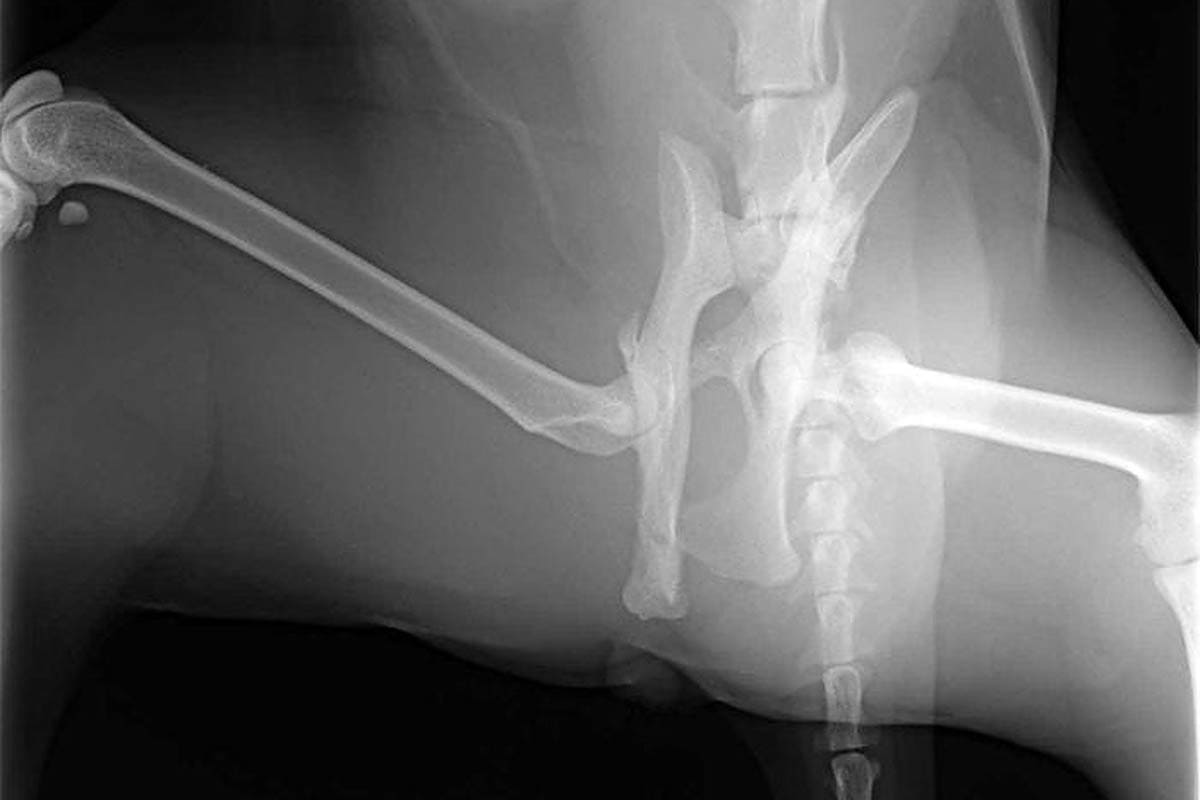

He Suffered A Fractured Pelvis And Dislocated Hip.

📌 7 June 2021 The Dog That Suffered A Fractured Pelvis After Being Hit By A Car Is Waiting.

Treatment of a fractured pelvis in cats. The pelvic bones, the pelvis (as in elvis), the pelvic girdle,. 2004 the most common injuries involved the extremities, head and neck, pelvis, and chest.

After 6 weeks cage rest and one failed attempt to pop the hip back, my vet. Sophie, a nine year old cat who suffered a broken pelvis after being hit by a car. She has a fractured pelvis and her tail is.